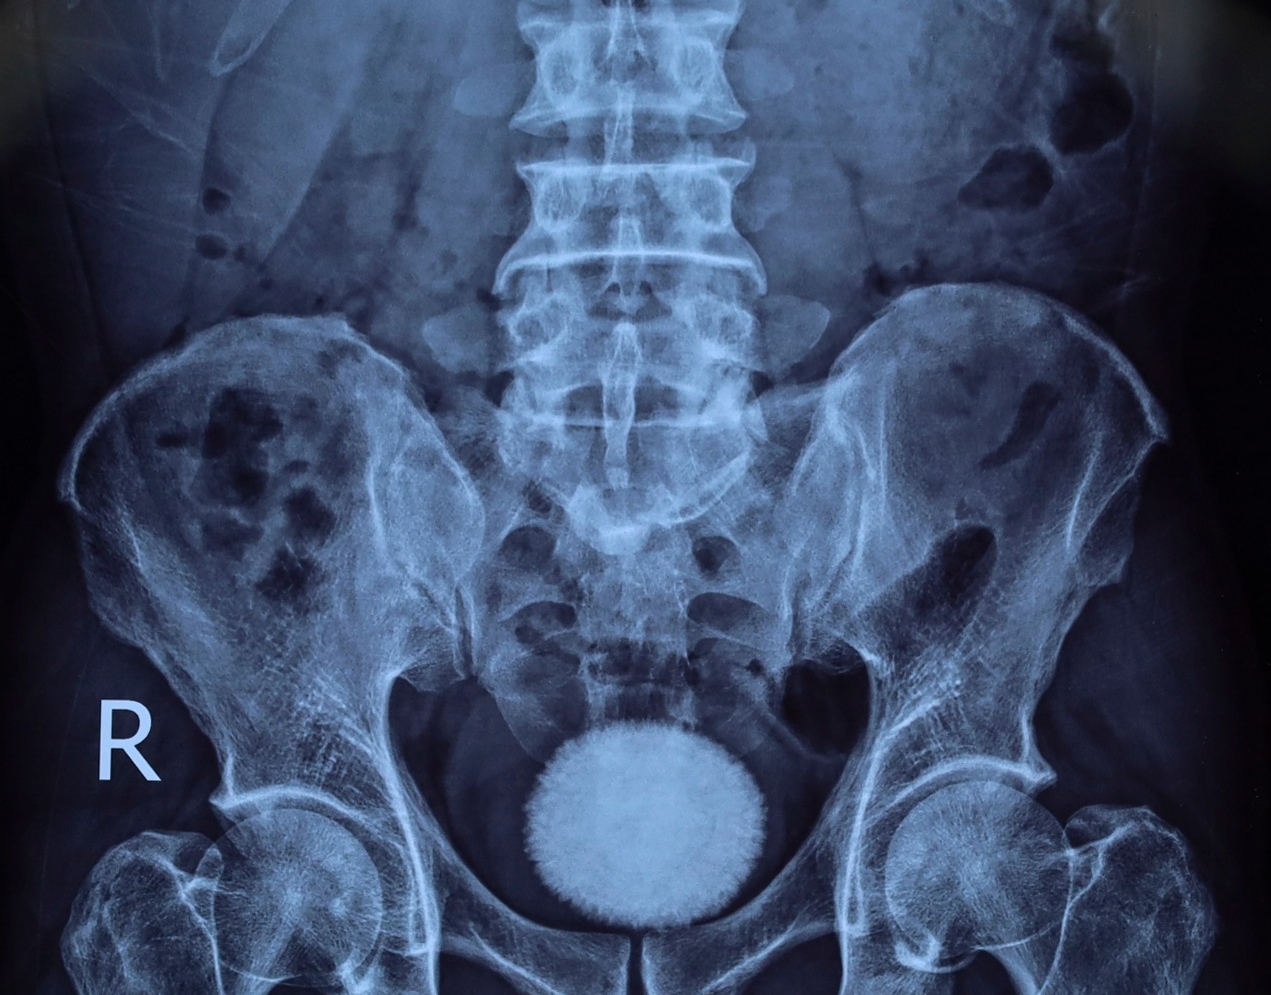

Trước đó, bệnh nhân đến khám trong tình trạng tiểu buốt, tiểu khó kéo dài, kèm đau vùng hạ vị. Qua thăm khám lâm sàng, siêu âm và chụp X-quang, các bác sĩ phát hiện trong bàng quang có viên sỏi kích thước khoảng 60×40 mm.

Viên sỏi bàng quang kích thước khoảng 60×40 mm được lấy ra sau phẫu thuật tại Bệnh viện Ngoại khoa 115 Nghệ An.